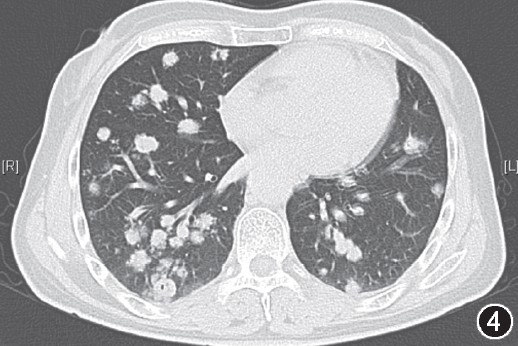

【答案公布】双肺多发结节及肿块影

【三甲读片】两肺多发结节,激素治疗后消失,你